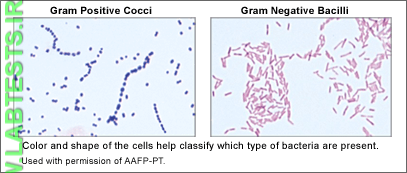

A Gram stain is used, along with a culture of the material from an infected site, to identify the cause of a bacterial infection. The Gram stain provides preliminary results on whether bacteria are present and the general type, such as the shape and whether they are Gram-positive or Gram-negative.

- Whether the bacteria are Gram-positive (purple) or Gram-negative (pink)

- Shape — round (cocci) or rods (bacilli)

A few examples of some medically significant bacteria and what they look like on a Gram stain include:

- Gram-positive cocci—Staphylcoccus aureus (Staph aureus) can cause skin infections and toxic shock syndrome; Streptococcus pneumoniae can cause pneumonia.

- Gram-negative cocci—Neisseria meningitidis causes meningitis while Neisseria gonorrhoeae causes the sexually transmitted disease gonorrhea.

The Gram stain involves applying a sample from an infected area or a sample of bacteria grown in culture onto a glass slide. The slide is then treated with a special stain and examined under a microscope by a trained laboratorian. The color and shape of the bacteria help classify which general types of bacteria are present.

Images used with permission of American Academy of Family Physicians-PT